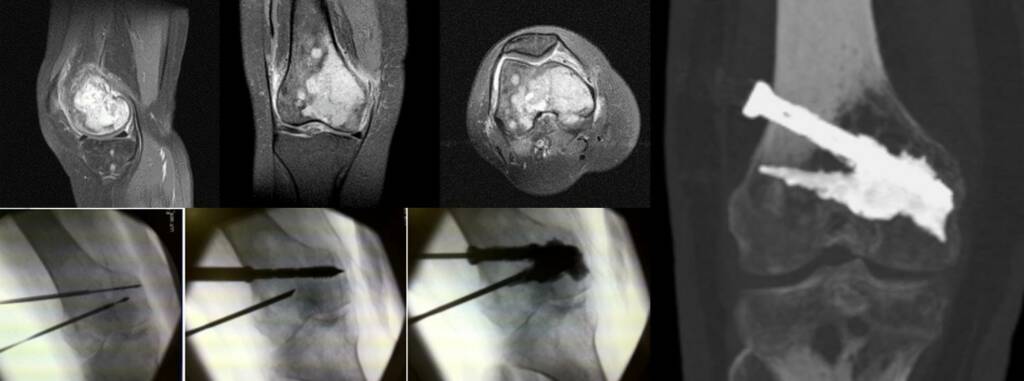

Percutaneous osteosynthesis is an advanced image-guided technique that stabilizes bone using screws, pins, or fixation systems inserted through small skin incisions.

It is particularly useful in long bones and complex skeletal structures affected by tumors or fractures.

Procedure

Performed under conscious sedation or general anesthesia:

Image-guided percutaneous placement of fixation devices

Optional combination with cement augmentation

- Integration with ablative treatments when indicated